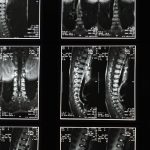

La décompression vertébrale consiste à appliquer des forces de traction sur la colonne vertébrale. Cette méthode a pour objectif de réduire la pression sur les disques intervertébraux. En créant une pression négative, la décompression peut aider à soulager la douleur liée aux hernies discales et à d’autres affections vertébrales.

La décompression vertébrale est une méthode non invasive qui utilise des principes biomécaniques complexes pour soulager la pression sur les disques intervertébraux. Grâce à des technologies avancées, cette approche permet de traiter efficacement les problèmes de dos sans recourir à des interventions chirurgicales. En appliquant des tractions mécaniques sur la colonne vertébrale, il est possible de créer une pression négative au niveau des disques, contribuant ainsi à l’aspiration des hernies et à la réduction des symptômes douloureux.

Les techniques de décompression spinale illustrent parfaitement ces progrès. En appliquant des forces décompressives automatisées, ces thérapies sont capables de mobiliser les articulations tout en réduisant la tension sur la colonne vertébrale. Ce processus permet de créer une pression négative dans le disque intervertébral, contribuant à aspirer les hernies et à diminuer les bombements des disques, ce qui est crucial pour les patients souffrant de douleurs dorsales.

En outre, la décompression neurovertébrale informatisée représente une autre avancée significative, permettant de contourner les contractions musculaires réflexes résultant de l’étirement de la colonne. Cette méthode offre un confort inégalé aux patients tout en optimisant les résultats cliniques. Les nouvelles approches non invasives rendent les traitements plus accessibles, réduisant ainsi la nécessité de recourir à des interventions chirurgicales, souvent redoutées par les patients.

Il est essentiel de noter que ces innovations ne se limitent pas seulement à l’application de techniques avancées, mais incluent également la recherche continue sur l’innervation et la biomécanique de la colonne vertébrale. Ces développements potentiels ouvrent la voie à des traitements plus ciblés et personnalisés pour chaque individu, renforçant l’idée que les innovations en décompression vertébrale représentent non seulement l’avenir, mais également une amélioration significative de la qualité de vie des patients souffrant de douleurs chroniques.